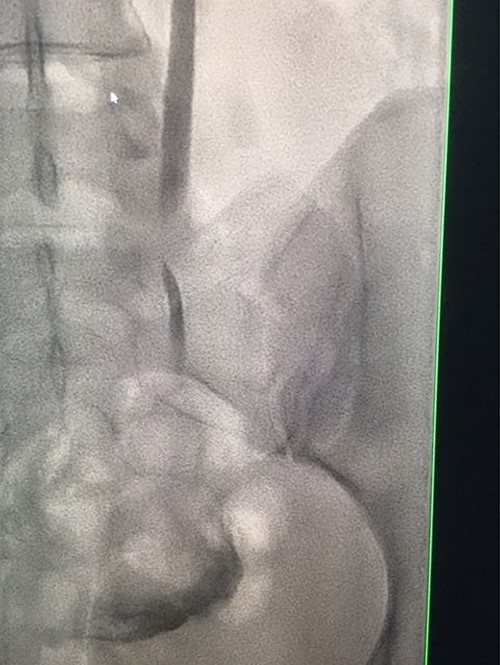

Computed tomography (CT) with urographic phase imaging demonstrated a right distal ureteric injury with leakage of urine into the pelvis and fistulation into the vagina (Figs 1 and 2). A diverting right percutaneous nephrostomy was inserted in the interventional radiology (IR) suite. An antegrade ureterogram at the same time demonstrated a complete discontinuation of the ureter which appeared retracted (Fig. 3).

Antegrade urethrogram showing proximal ureter opacification with contrast, with an abrupt end point consistent with transected right distal ureter.